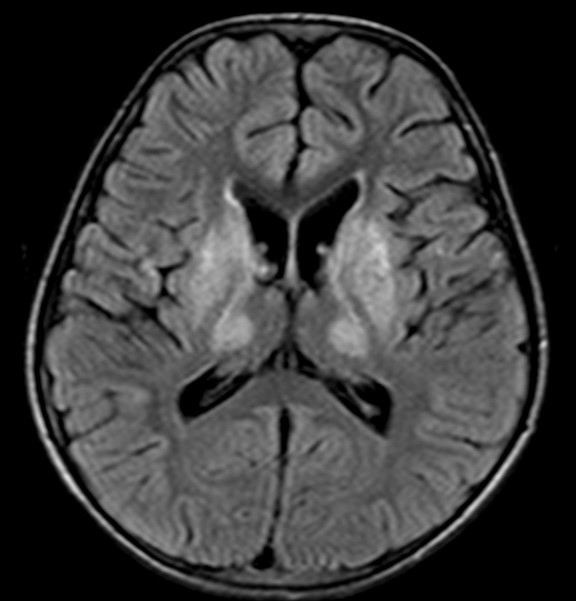

An initial CT head is reported as inconclusive and thus an urgent MRI brain is performed.

Q3: Comment on the MRI results. What is the diagnosis?

This is a FLAIR MRI (T2 weighted with CSF signal subtracted). There is hyperattenuationin both basal ganglia, which would explain his parkinsonian signs (rigidity, tremor).Combined with the liver dysfunction, the most likely diagnosis in this case is Wilson’sDisease.

Image 1: Case courtesy of Dr Paresh K Desai, Radiopaedia.org. From the case rID: 12107